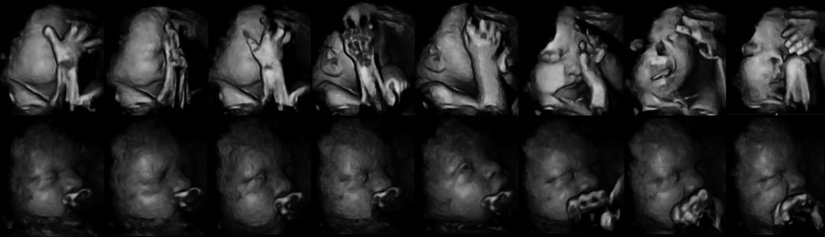

Aşağıda gördüğünüz, iki sıra bebek fotoğrafı. Bu fotoğrafları özel kılan şey, 4 boyutlu ultrason (3 boyutlu çekim + zaman) yöntemiyle kaydedilmiş olmaları. Ancak sadece bu da değil... Üstteki sıra, annesi sigara içen bir fetüse ait. Alttaki ise içmeyene...

İlk etapta çok fark görülemeyebilir. Ancak fotoğraf serisini soldan sağa doğru dikkatle takip edecek olursanız, üstteki bebeğin ağzını yüzünü hareket ettirdiğini ve eliyle yüzüne dokunmaya çalıştığını göreceksiniz. Alttakinin yüzü ise normal bir şekilde durmaktadır ve elleriyle yüzüne dokunma çabası yoktur.

"Ee, ne var bunda?" diyebilirsiniz... Sorun şu ki, bebekler hamileliğin erken evrelerinde yüzlerini buruşturmaya ve elleriyle yüzlerine dokunmaya meyillidirler. Bu normaldir. Ancak hamilelik süresi ilerledikçe, bu davranışlar giderek azalır ve bebek daha ziyade kollarına bacaklarına ve vücudunun geri kalanına dokunarak özellikle uzuvlarını tanımaya çalışır. Bunun nedeni, sinir sistemi ve beyni geliştikçe, uzuvlarını daha aktif olarak kullanmaya başlamasıdır. Yüzüne olan ilgisi azalır. Dahası, yüzünü de buruşturmayı bırakır.

Fakat Durham Üniversitesi tarafından yapılan yeni bir araştırmada, hamilelikte sigara içen annelerin yavrularında bu gelişim evrelerinin yavaşladığı gözlendi.[1] Yani üstteki seride, bebek aslında artık bırakmış olmasına rağmen yüzünü buruşturmaya devam ediyor ve yüzüne dokunmaya çalışıyor. Alttaki seride (sigara içmeyen anneni bebeği) ise normal gelişim görülüyor. Uzmanlar bu farklılığı sigaranın sinir sisteminin gelişimi üzerindeki yavaşlatıcı ve olumsuz etkiye bağlıyor.